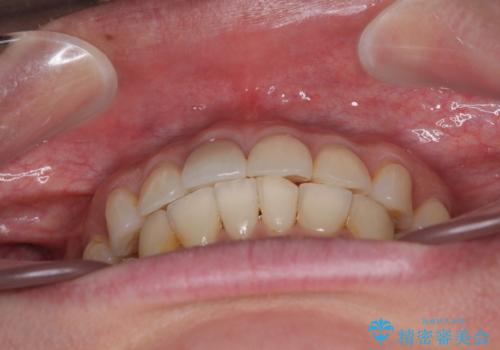

- 全体的なデコボコと左下乳歯部の欠損を気にして来院された患者様です。

乳歯が抜け落ちた後の後続永久歯が欠損しているため、スペースが残っておりました。

口元の突出感を気にしているのであれば欠損スペースを利用して抜歯矯正を行うことも可能ですが、横顔の印象はスッキリとしている状態であったため、矯正治療でスペースを閉じきることは不可能と判断し、インプラントによる補綴治療を行うこととしました。

第二小臼歯の欠損によるが乳歯残存や欠損が多く、この乳歯は後続永久歯に比べて幅が非常に大きいため、教聖地料によるスペースクローズが難しいことが一般的です。